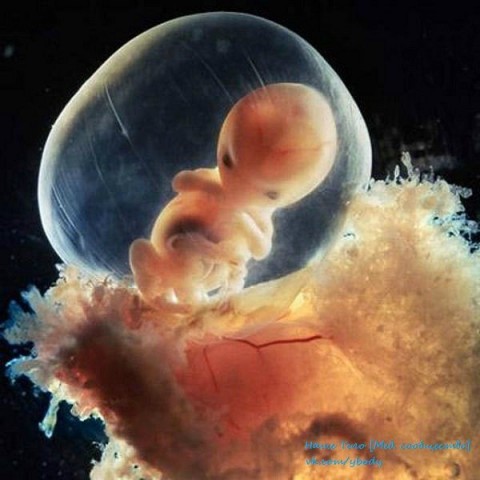

8 недель. Быстрорастущий эмбрион хорошо защищен во чреве

матери. С помощью электронного микроскопа Нильссон смог увеличить

изображение в сотни тысяч раз

Скелет в основном состоит из гибкого стержня и сети кровеносных сосудов, видимой сквозь тонкую кожу